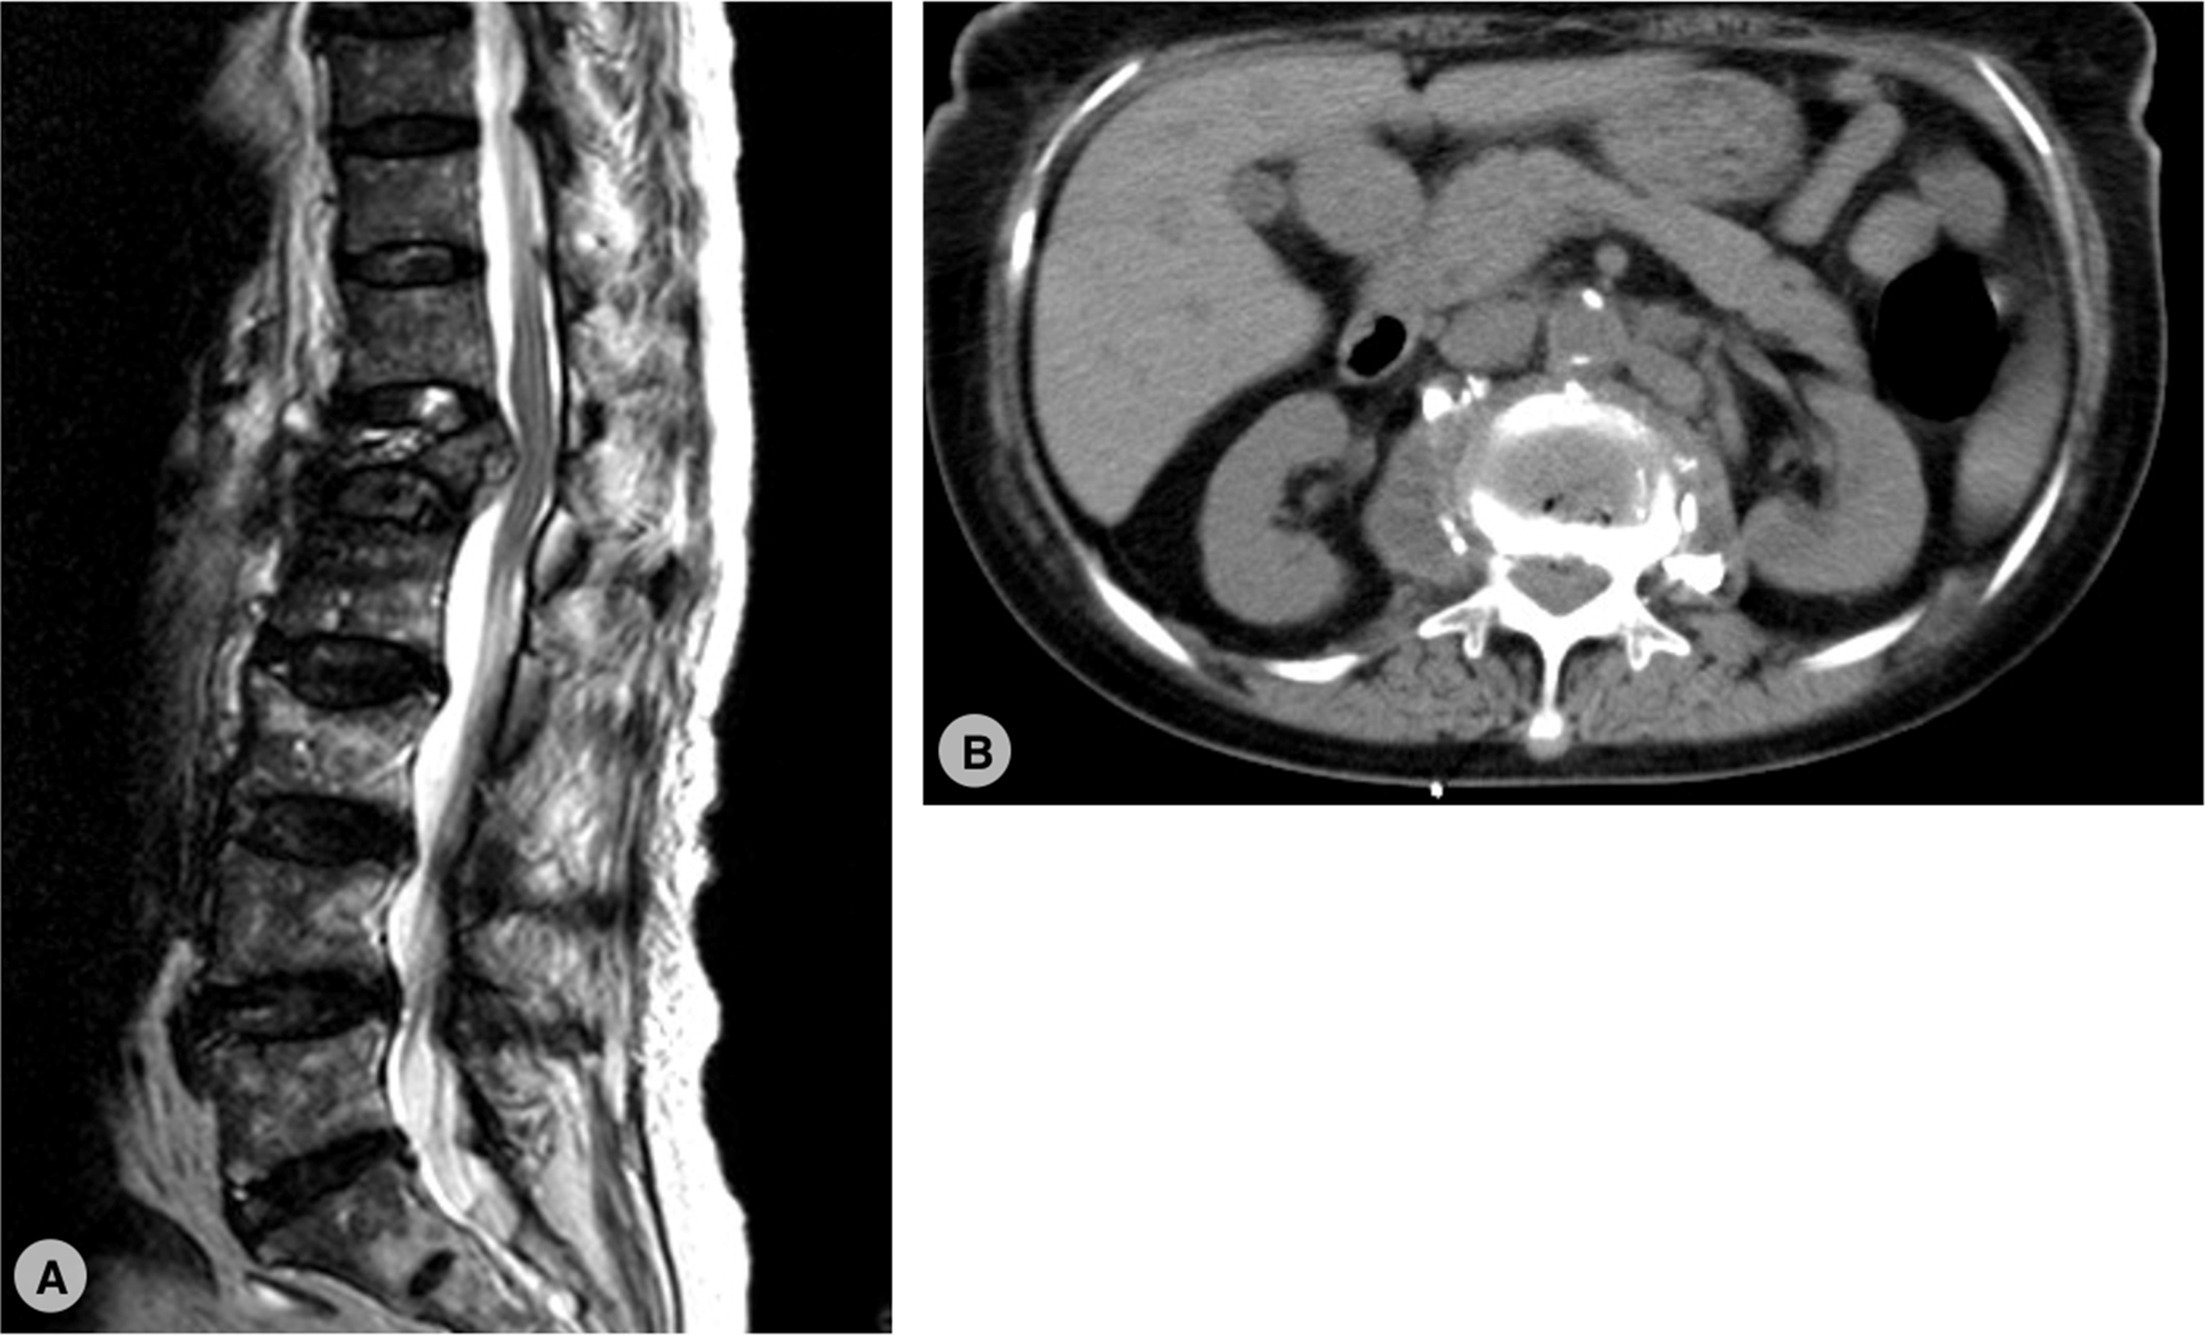

Infection

Infective spondylodiscitis is a rare but serious infection of the intervertebral discs and the adjacent vertebrae in the spine. It occurs when bacteria, fungi, or other pathogens invade these areas, leading to inflammation and potential damage to the spinal structures. This condition is most commonly caused by bacterial infections, particularly from organisms like Staphylococcus aureus or Escherichia coli.

In India, the spondylodiscitis caused by tubercle bacilli is fairly commonly known as Koch’s / Potts Spine.

It can result from a direct infection following surgery, trauma, or an intravenous drug use, or through hematogenous spread from another infected part of the body.

It most commonly involves the dorsal spine or dorsolumbar junction.

The symptoms of infective spondylodiscitis typically include severe back pain, fever, and difficulty moving, which may worsen over time if not treated. Patients may also experience neurological symptoms like numbness, weakness, or paralysis if the infection spreads to the spinal cord.

Diagnosis usually involves imaging studies such as MRI, along with blood cultures and biopsy to identify the specific pathogen causing the infection.

Treatment of infective spondylodiscitis generally involves long-term antibiotic therapy, often administered intravenously, followed by oral antibiotics

In severe cases, with spine instability or neurological symptoms like numbness, weakness, or paralysis and bowel/bladder involvement surgery is be required to drain abscesses, remove infected tissue, or stabilize the spine.

If left untreated, the infection can lead to permanent spinal damage, abscess formation, or even sepsis, a life-threatening condition. Early diagnosis and prompt treatment are essential for a favourable outcome.

Infective spondylodiscitis remains a challenging condition, requiring a multidisciplinary approach for effective management. Awareness of its symptoms and timely intervention are crucial for preventing long-term complications.